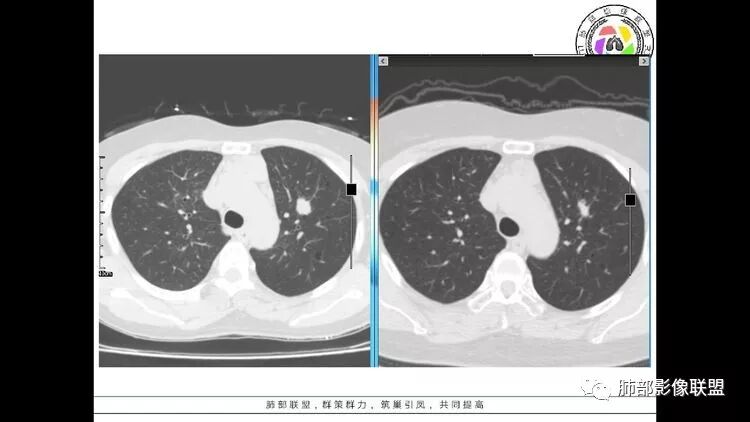

患者中年女性,因右眼红痛1天就诊。胸CT:双肺多发囊性变及结节影,囊以中下肺为多,部分囊内可见分隔及肺动脉,结节部分为实性,部分为混合性,边缘光滑,未见明显毛刺、棘突、胸膜牵拉及血管集束征象。双中下可见支气管扩张及树丫征。淋巴结无明显肿大。综合考虑:一元淋巴细胞间质性肺炎。多元鉴别肺腺癌并转移等恶性病变。

中年女性,双肺多发囊性变,以中下肺为主,病变边缘可见肺动脉,部分囊内可见分隔及肺动脉,左肺上叶较大结节,可见分叶、月牙铲,左肺下叶、右肺中叶磨玻璃病灶,边界清楚,内有空泡,结节,可见尖后段 右肺上叶前段 右肺下叶外基底段 结节影,边界清楚,纵隔淋巴结肿大,

考虑腺癌,淋巴管肌瘤病?LIP?